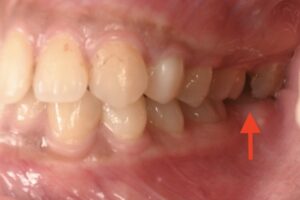

噛み合わせを見ています。

矢印の部分です。

根管治療後の歯は失活歯(しっかつし)といって歯髄がないため歯が脆くなります。

噛む力で歯が折れてしまい亀裂(クラック)が入ると、先ほどのようなレントゲンの炎症像がひろがるのです。